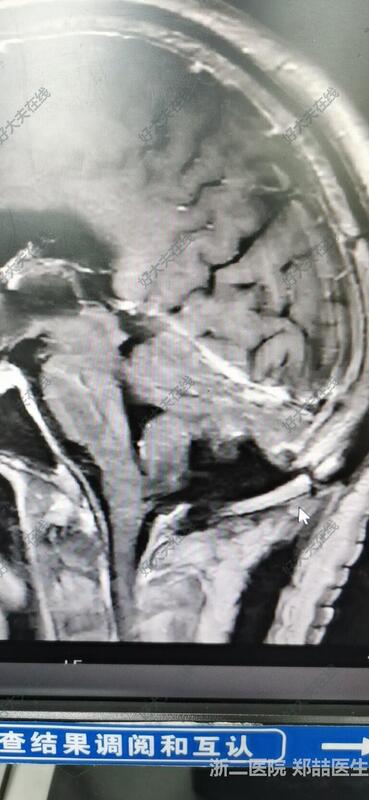

71岁男性,头晕1个月,行走不稳,伴恶心呕吐。头磁共振检查发现后颅窝占位。我院报告淋巴瘤或髓母细胞瘤。个人考虑脑膜瘤可能大,基底广泛。

后正中入路,切除肿瘤,基底广泛,冰冻考虑脑膜瘤。

患者恢复良好,可下地活动,头晕好转,无其他不适。头磁共振复查提示肿瘤全切。